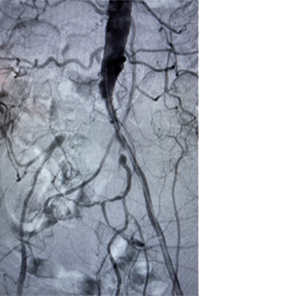

• initial-angio.png

Angiographie initiale

Images avec l’aimable autorisation du Dr Norby.

Les résultats individuels peuvent varier.